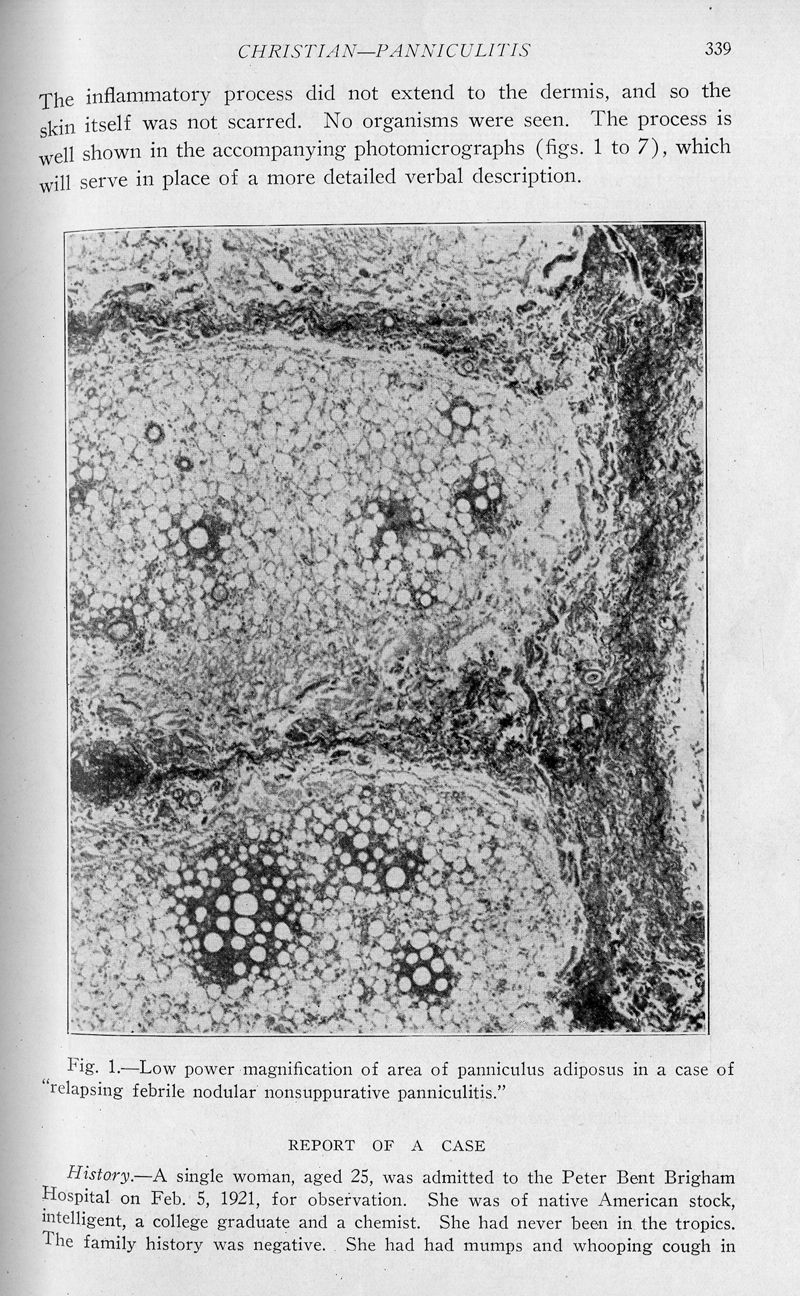

In : Archives of internal medicine (1908), 1928, Vol. 42, pp. 338-51